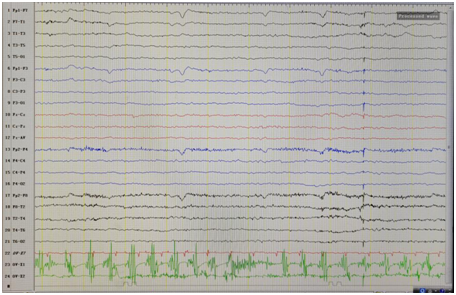

近1个月来,患者无明显诱因反复出现恶心、腹部不适,随后出现晕厥,无肢体强直、抖动,无心前区不适,持续几秒钟缓解。神经科查体未见阳性定位体征。完善头MRI、头CT均未见异常。完善视频脑电图如下:

日本光电脑电图怎么样【特色门诊】被“癫痫”困扰?癫痫门诊为您带来精准治疗_https://www.jmylbn.com_新闻资讯_第12张

视频脑电图见:右侧前头部棘-慢波放电。

明确诊断为:癫痫,予拉莫三嗪治疗,近3个月患者无发作。